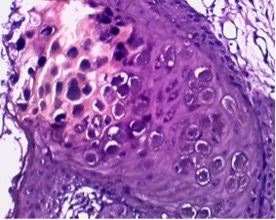

Differential diagnoses which were considered at this point included molluscum contagiosum (MC), human papilloma virus and cutaneous cryptococcosis. A skin biopsy revealed large cytoplasmic eosinophilic inclusion bodies (Henderson-Paterson bodies) which are pathognomonic for MC [1] (Figs. 2 and 3).

Figure 2.

(Left image) A skin biopsy including epidermis and dermis showing an inverted lobule of hyperplastic squamous epithelium extending into the dermis (H&E stain ×20 magnification). (Right image) Large eosinophilic viral inclusion bodies also known as Henderson-Paterson or molluscum bodies (H&E ×40 magnification)

Figure 3.

Giemsa stain highlighting molluscum bodies